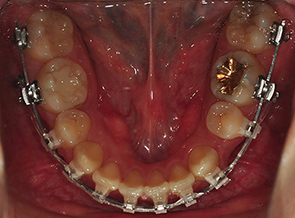

그리고는 고무줄도 새로운것으로 갈고 치아 중심선이 잘 맞는지도 봐주셨어요. 이~ 해서 위아래 치아선이 직선으로 잘 맞는지 봐주셨어요. 고무줄도 상악과 하악 둘다 새로운것으로 갈았어요

킬본장치, 상악에 새로운 고무줄로 갈았는데 아주 팽팽해서 새로운걸 하긴했구나하는 생각이 확들었어요 ㅋㅋ

다시 치과에 내원하였더니 원장선생님이 '어?' 그러시면서 다시 봐주셨어요 ㅋㅋ 저는 집에가는길이 고무줄이 끊어진것 같다고 말씀드렸는데 고무줄이 두줄로 된 부분중에 한줄이 끊어진것이었어요

고무줄을 교체해주시면서 의사선생님이 설명을 해주셨는데 두줄인것에서 하나만 끊어졌을때는 굳이 내원하지 않아도 된다고 하시더라구요 하나만 연결되어있어도 크게 문제 되지 않는다고

말씀해주셔서 안도의 마음과 함께 새로운 고무줄로 교체를 하였습니다.